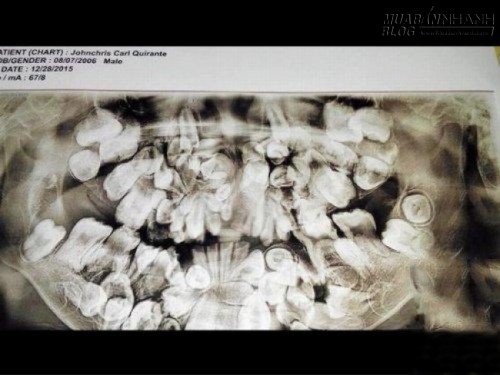

Phim chụp X-quang vòm miệng chi chít răng của John

Những chiếc răng sữa khi rụng sẽ được thay thế bởi răng trưởng thành. Nhưng vấn đề đơn giản đó lại trái ngược hoàn toàn đối với Johncris Carl Quirante, một cậu bé 9 tuổi sống tại Cebu, Philippines. Khi John còn bé, thay vì có 20 răng sữa như những đứa trẻ bình thường thì cậu lại có ít nhất 50 chiếc mọc quanh vòm miệng. Bố mẹ John vì không đủ tiền cho cậu bé đến nha sĩ nên đến khi được 5 tuổi, John đã có tới 150 chiếc răng. Tình trạng xấu đi cho tới thời điểm hiện tại, số lượng răng có trong vòm miệng John đã lên tới xấp xỉ 300 chiếc.